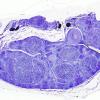

PERIPHERAL NEUROPATHY

1 NORMAL NERVE ANATOMY

3 Normal Plastic Sections (2)